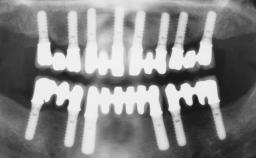

Immediate Loading of Four Implants in the Mandible and Six Implants in the Maxilla and Final Restoration with a Full-Arch Metal Framework FDP and a Full-Arch CAD/CAM Zirconia Framework FDP

# of Implants 10

Bone Augmentation Horizontal|Simultaneous